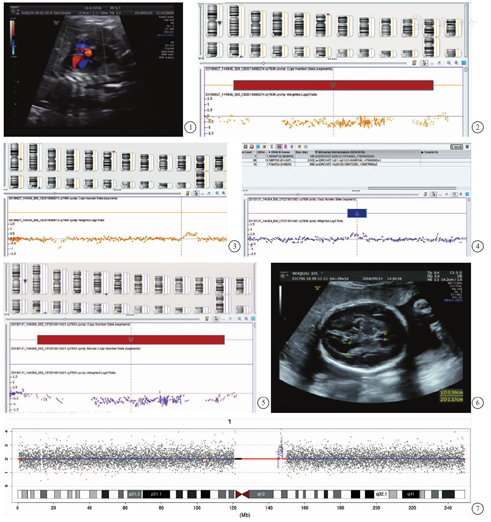

孕妇1 30岁,G1P0,否认家族遗传病史,孕30+4周系统超声发现胎儿室间隔缺损(图1)。经夫妻双方知情同意,在我院行羊膜腔穿刺术。胎儿染色体核型未见异常。染色体微阵列分析(chromosomal microarray analysis,CMA;采用Affymetrix CytoScan 750K)结果提示胎儿染色体1q21.1q21.2区存在2.002 Mb缺失,5q35.3区存在0.182 Mb重复(图2、图3)。孕妇染色体1q21.1q21.2区存在1.862 Mb缺失,5q35.3区存在0.164 Mb重复(图4、图5)。胎儿父亲CMA检测未见异常。孕妇在遗传咨询后选择引产,娩出胎儿因孕周小未发现明显畸形,未对引产儿进行病理学检查。本研究通过了本院医学伦理委员会的审查(2020-382号)。

孕妇2 32岁,G2P0,首次妊娠孕8周自然流产,否认家族遗传病史。第二次妊娠孕29+3周系统超声发现胎儿左侧侧脑室轻度扩张1.17 cm(图6)。经夫妻双方知情同意,在我院行羊膜腔穿刺术。胎儿染色体核型未见异常。胎儿羊水弓形虫、巨细胞病毒、单纯疱疹病毒、风疹病毒、微小病毒B19 PCR定量检测均未见异常。CMA检测提示其1q21.1-q21.2区存在约1.98 Mb重复(图7),夫妻双方染色体及CMA检测均未见异常。孕妇在遗传咨询后选择引产,娩出胎儿因孕周小未发现明显畸形,未对引产儿进行病理学检查。孕妇签署知情同意书。本研究通过了本院医学伦理委员会的审查(2020-382号)。